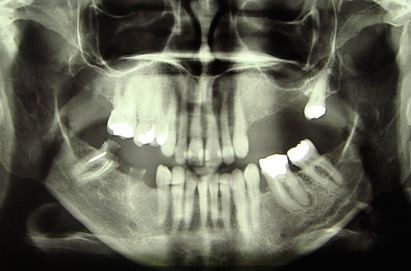

1) Панорамная рентгенограмма больной 57 лет, по показаниям удаление зубов нижней челюсти.

1) Панорамная рентгенограмма больной с частичной адентией на верхней челюсти слева. Планируется удаление корней 23 и 27 зубов и установка 5 имплантатов в области зубов с 23 по 27. В области зубов 25, 26 и 27 будет проведена направленная регенерация костной ткани «синус лифтинг» с одномоментной установкой имплантатов.

1) Панорамный снимок, пациентка 62 года, отсутствуют 36 и 37 зубы, планируется имплантация 3-х имплантатов в области отсутствующих зубов.

1) панорамные рентген пациента до лечения